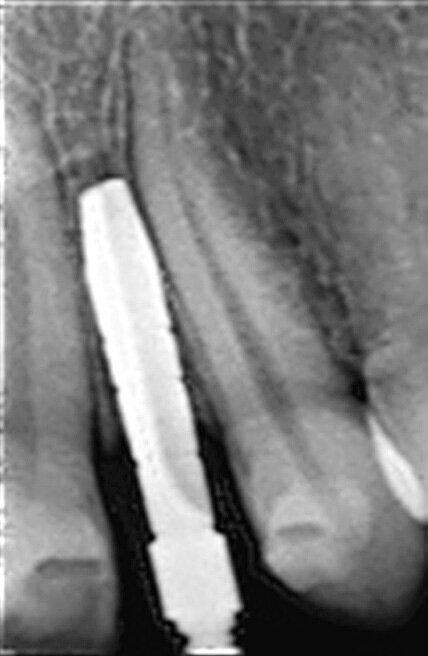

Fig. 1 : Radiographie panoramique. Il faut noter l’espace restreint en position de la dent 22.

Fig. 7 : Présentation radiologique de la technique d’ouverture de l’espace interradiculaire. Il faut noter l’insertion des alésoirs manuels de 2,5 mm et 3,0 mm entre les racines, afin de préparer l’espace pour l’implant de Ø 3,0 mm, mis en place à 3,0 mm sous le niveau de l’os crestal.

L’implant a été mis en place au moyen d’un instrument spécial pour l’insertion d’implant, qui permet au praticien de pousser l’implant fermement, en appliquant une pression précise dans l’ostéotomie (Fig. 5). La dernière étape a consisté à introduire complètement l’implant au moyen du maillet, et de l’instrument d’insertion fixé à la poignée de serrage droite. L’implant étroit était dès lors bien positionné entre les deux racines (Fig. 6). L’implant de 8 mm de long et de Ø 3 mm a été inséré par l’application d’une pression dans l’ostéotomie, et l’utilisation du maillet et de l’instrument d’insertion à 3 mm sous le niveau de l’os crestal (Fig. 7). La seconde phase du traitement a été réalisée après six mois de cicatrisation et a consisté à désenfouir l’implant. Un pilier ayant un corps de Ø 2 mm et une base hémisphérique de Ø 4 mm a été choisi pour connecter les couronnes provisoires à l’implant. Il est important de veiller à la bonne cicatrisation du tissu mou autour du contour coronaire adéquat, et celle-ci peut être obtenue par une modification du profil d’émergence de la couronne provisoire jusqu’à la formation des papilles. Après la cicatrisation complète du tissu mou, la dernière empreinte a été prise et la couronne définitive a été scellée sur le pilier en titane (Figs. 8 et 9).